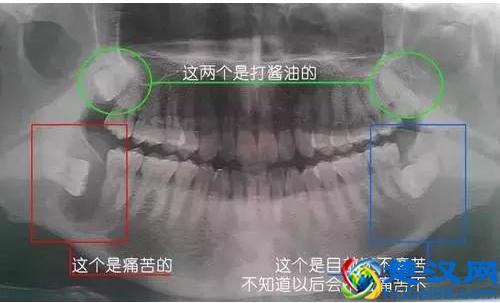

有的人的智齿是躺着生长的,它是埋在牙龈下的,外面是看不出来的;

因此建议大家不妨拍个口腔全景片,这样就一目了然,能够看到智齿的各种情况。